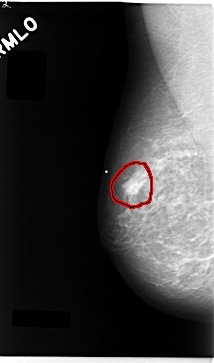

C_0043_1.RIGHT_MLO

FILE: C_0043_1.RIGHT_MLO.OVERLAY

TOTAL_ABNORMALITIES 1

ABNORMALITY 1

LESION_TYPE MASS SHAPE IRREGULAR MARGINS MICROLOBULATED

ASSESSMENT 5

SUBTLETY 5

PATHOLOGY MALIGNANT

TOTAL_OUTLINES 1

BOUNDARY